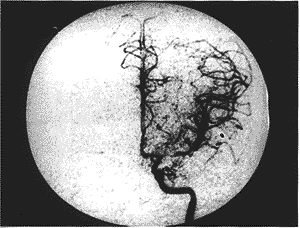

1.17例烟雾病患者的CDE和DSA检查结果:在17例烟雾病患者的102条大脑主要动脉中 ,CDE 显示49条血管闭塞,(ACA 27条、MCA 20条、PCA2条),而DSA显示51条完全闭塞(ACA 23条、 MCA 22条、PCA 6条),二者诊断相符者44条(ACA 23条、MCA 19条、PCA 2条)。CDE显示15条 血管狭窄,其中血流明显降低者12条(ACA 1条、MCA 5条、PCA 6条),血流明显升高者3条( 均为MCA),而DSA诊断为狭窄者12条(ACA 4条、MCA 6条、PCA 2条),二者诊断相符者8条(AC A 1条、MCA 5条、PCA 2条),如图1、2。CDE显示38条血管正常(ACA 6条、MCA 6条、PCA 2 6条),而DSA显示39条正常(ACA 7条、MCA 6条、PCA 26条),有1条ACA,DSA显示正常而CDE 未发现血流 信号。102条血管中,有7条CDE显示为低速血流信号者(MCA 3条、PCA 4条),DSA显示为完全 闭塞。有4条CDE显示为完全闭塞者(ACA 3条、MCA 1条),DSA显示为狭窄。

图1 DSA示左侧MCA起始段狭窄